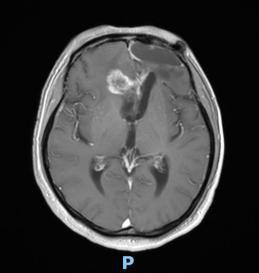

44歲的郭先生(化姓)為膠質(zhì)瘤復(fù)發(fā)患者,復(fù)查發(fā)現(xiàn)顱內(nèi)占位進(jìn)行性進(jìn)展1周,MRI檢查提示瘤體已累積到胼胝體,且瘤體位置較深,手術(shù)難度極高。面對這一挑戰(zhàn),王虎教授團(tuán)隊(duì)決定采用多種先進(jìn)技術(shù)輔助手術(shù),其中最為引人注目的就是首次引入的細(xì)胞級顯微鏡EndoSCell?。該設(shè)備是目前全球唯一實(shí)時(shí)在體細(xì)胞級顯影的儀器,可以輔助醫(yī)生從細(xì)胞層面區(qū)分腫瘤組織與正常組織,從而做到細(xì)胞級精準(zhǔn)切除。

患者術(shù)前核磁影像